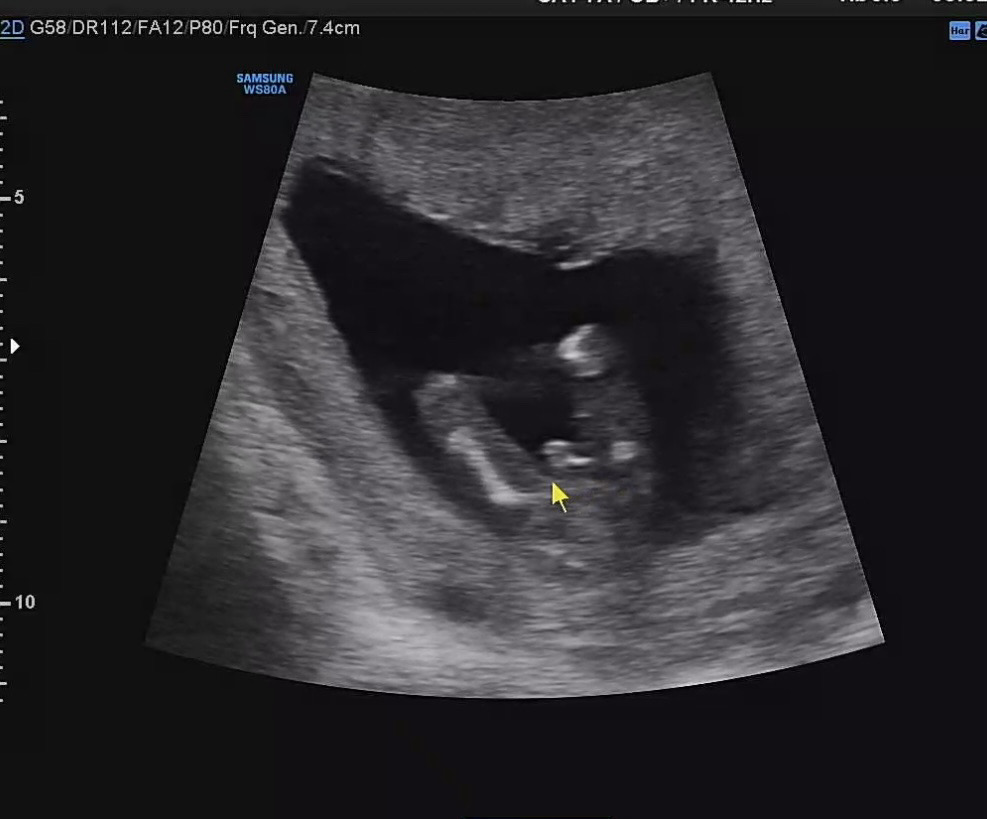

다리사이에 동글한거 꽈추인가요..? 저렇게 동글동글할수가있는가유..... 허허 13주6일입니다! 각도법은 딸이라고 하셨는데 의사선생님도 긴가민가 하시다구했어요 ㅎㅎ

딸같아요!! 저희남편도 딸같대요 ㅎ

저도 12주에 뾰족하게 튀어나와있었는데 여자아이도 남자아이도 16주전에는 남자성기처럼 튀어나와있어서 16주후에 정확히 알 수 있대요!

엇 너무 명확한 존재감인데요 ..?! 아들 아닌가요 🤣